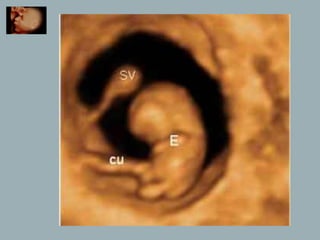

Corte a las10 semanas .

Se identifica claramente el saco

vitelino